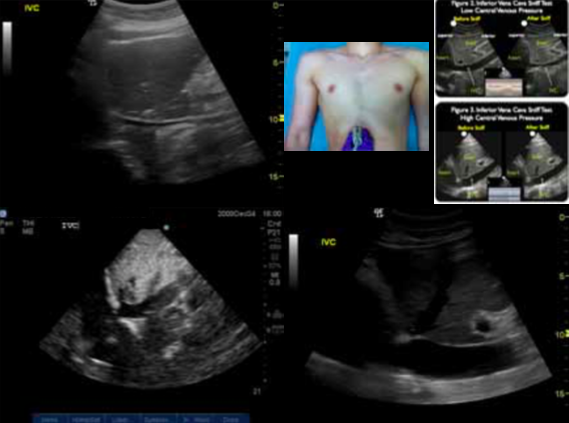

Noninvasive way to look at a patient’s volume status

IVC collapses when patient breaths in if patient is hypovolemic ( 2cm = high central venous pressure, this is how it will look if someone has a massive PE, tension pneumothorax or pericardial tamponade.